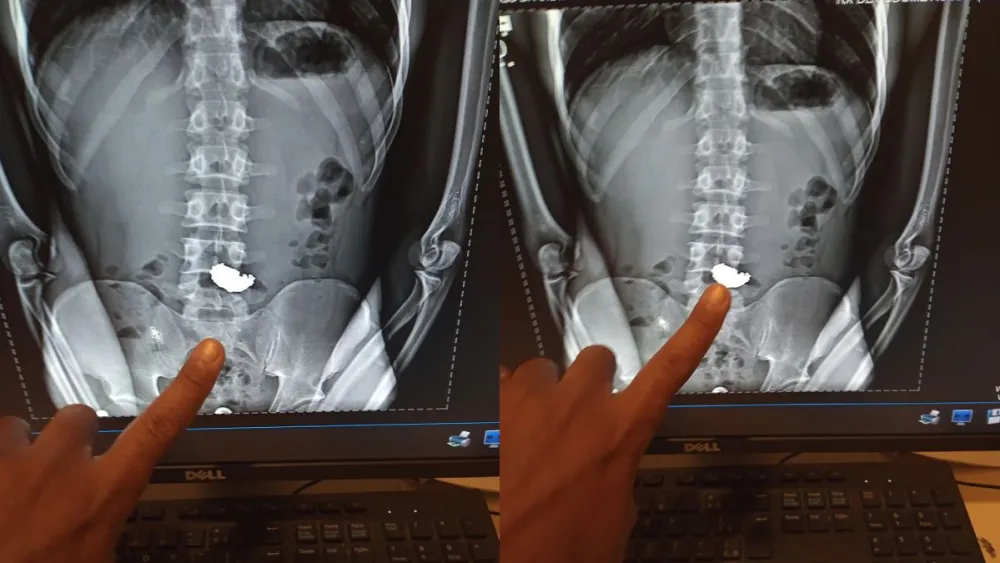

O jovem foi levado ao Hospital Odilon Behrens, na região Noroeste da capital, onde um exame de raio-X confirmou a presença da corrente de ouro em seu estômago. Com um extenso histórico criminal que inclui roubos, furtos e tráfico, ele foi encaminhado à Delegacia de Plantão da Polícia Civil.